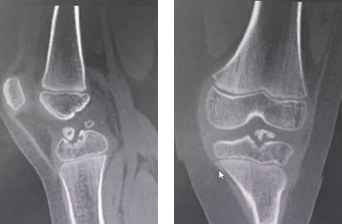

“小孩子嘛,本以为就是贪玩摔了一跤,没什么大不了,但这两年间,孩子时不时的总说左膝不舒服,直到昨天活动量大了,孩子疼得直哭,赶紧带他来瞧瞧……”强强的妈妈向张主任诉说着孩子的病情,越说越难过。在初步了解孩子病情后,张传开主任对孩子的膝关节进行了仔细检查,拍片显示:左胫骨平台陈旧性骨折(髁间脊陈旧性骨折)。

术前

张传开主任介绍:孩子骨折愈合的速度比较快,像成人骨折愈合一般需4周时间,而孩子一般只需2周。很多孩子都会如强强这样,在表面症状消除后,孩子自己就觉得“没事了”,但实际上很有可能已伤到骨骼及周围组织,这种情况如果一直拖着不治疗,不仅会加剧病情,还会影响孩子的生长发育。